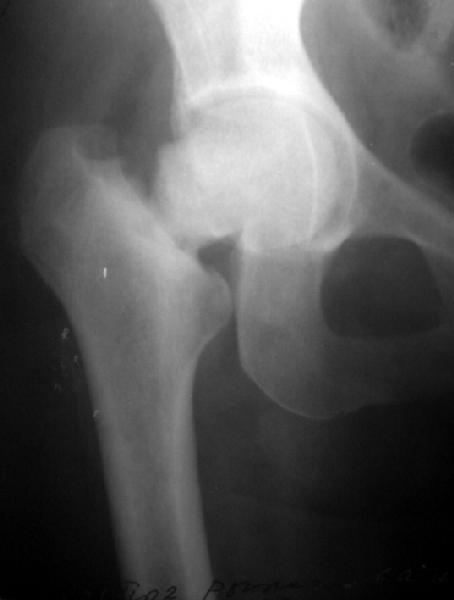

Сегодня сделали, прилагаю. Качество не очень, но положение отломков видно.

It looks like there is an early fatigue (stress) fracture of the opposite hip as well. I would fix both hips with screws, then get a bone mineral density and other endocrologic work-up

?????Is there a lesion on the opposite neck too!!!!

Напоминаю, что упала больная 5 ноября, но до этого несколько месяцев жаловалась на боли в тазобедренном суставе. А вообще "что-то не то" с

этой областью было года два. За все это время уменьшения амплитуды движений, с ее слов, не было. И вот сегодня прислали ее снимок,

сделанный 1 ноября, до есть за 4 дня до падения. Вроде есть там что-то типа лоозеровской зоны.

Может, все-таки усталостный перелом?